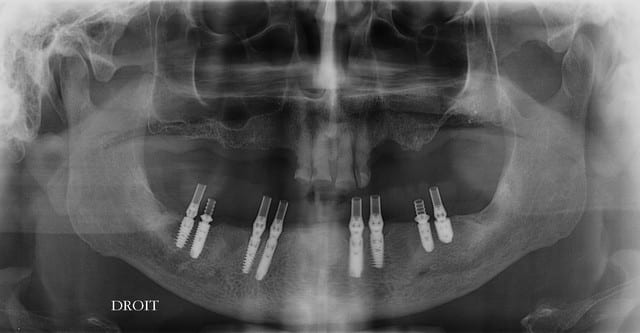

pxav, je comprend pas trop la position des implants, "2 par 2"

Tu as une radio (pano) après la pose ?

c'est un all-on-four version prudente ;-)

Au contraire, ça me semble compliquer les choses pour l'entretient. La proximité implantaire nuit à la stabilité osseuse.

Faudrait une p'tite radio

voilà pour toi Ceramik

Coucou, quelle technique bizarre. Pourquoi faire 2 par 2 comme cela ?

puis y en a pas 2 pareils cote à cote !

çà devait être pour évaluer le comportement des Axiom PX vs les Axiom REG...;-)

plus sérieusement, avec les biphosphonates, amha au cas où quelques implants partent à la benne, çà permet de limiter le risque de devoir profondément remanier le plan de ttm...non?

Ou un all on 4 immédiat avec 4 implants en nourrice au cas ou

à mon avis si problème avec les bp ça ne va pas concerner un implant mais l'os en général, donc non ce n'est pas la raison du 2 par2.

en réalité, je ne m'étais jamais posé la question car j'ai raisonné, os/position/prothèse et je pense que c'est un hasard si ils sont 2 par 2.

le choix axiom/reg est fixé aussi fonction de l'os, pas de question de stock ou de comparaison.